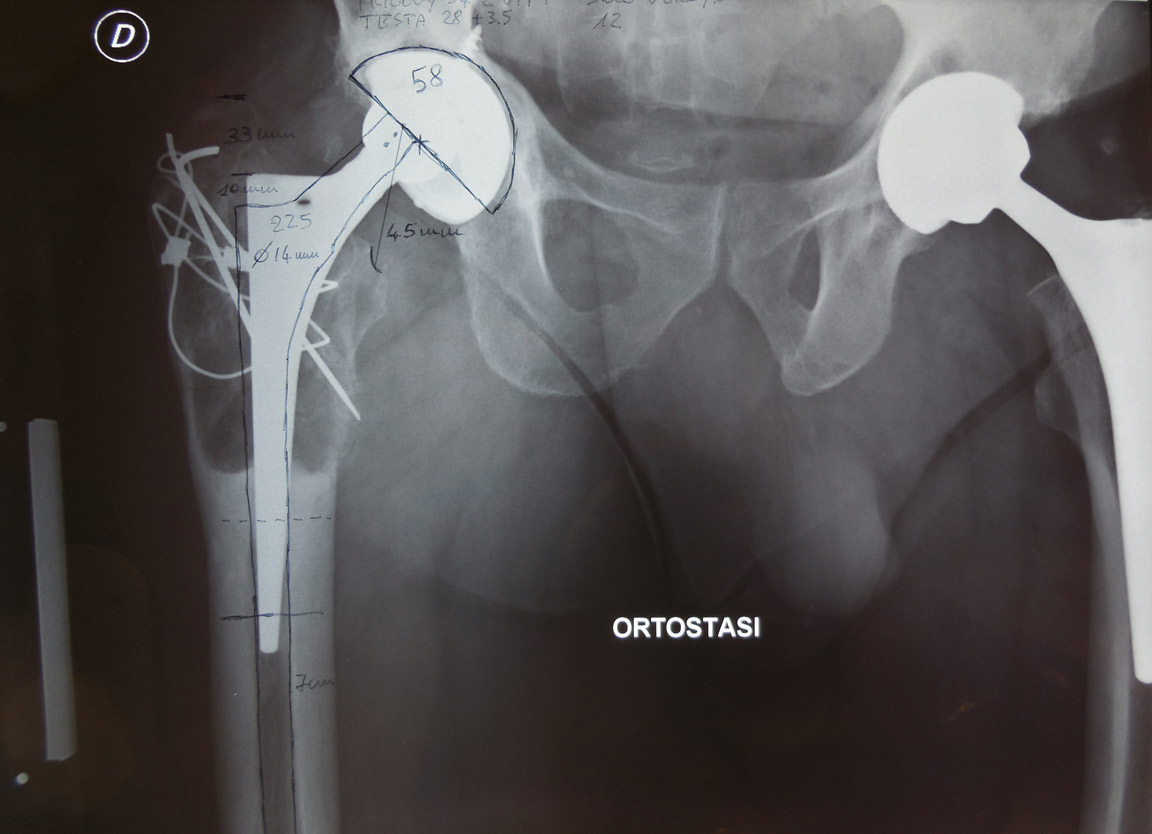

Fig. 1 Paziente con protesi di anca destra operata già 3 volte ( a causa di un’infezione) 10 anni prima. A sinistra protesi di primo impianto operata 3 anni prima.Il cotile è mobilizzato.L’inserto in polietilene (plastica) è usurato e la testa femorale è risalita: la polvere di polietilene dovuta all’usura, entra nell’interfaccia tra protesi e osso ed è causa della cosddetta “malattia da polietilene” che è responsabile dell’ usura dell’osso e dello scollamento della protesi.Nel caso in questione l’usura del femore ha causato un assottigliamento delle corticali così grave che esse presentano un aspetto a guscio d’uovo. La parte terminale della protesi invece è incarcerata e necessiterà, nel corso del reintervento, dell’ apertura (“a panino”) del femore per poter posizionare la protesi definitiva.Si vedono ancora i mezzi metallici utilizzati nel primo intervento, probabilmente per una frattura del gran trocantere.In sovrapposizione si vede il disegno della nuova protesi che verrà impiantata.